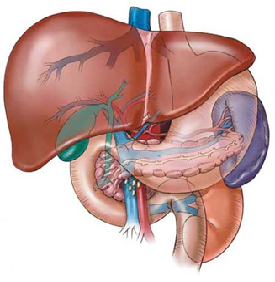

To reach a distinguished level and adopted in accordance with quality standards in the treatment of liver, pancreas and gallbladder diseases at the national level within five years and internationally within 10 years.

Improving the health of the community in the field of treatment of liver, pancreas and gallbladder diseases by providing high quality medical service and raising the efficiency of the medical team and excellent medical research.